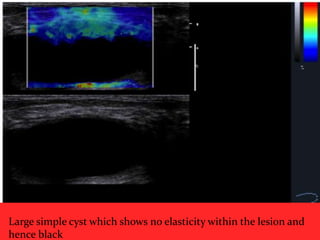

 Elastography has the potential to

differentiate complicated cysts form

solid masses.

 Shear-wave propagation does not occur

in cysts and therefore cysts should have

elastography values of zero and will

appear mostly black or homogeneously

blue on the color overlay elastogram

Large simple cyst which shows no elasticity within the lesion and

hence black